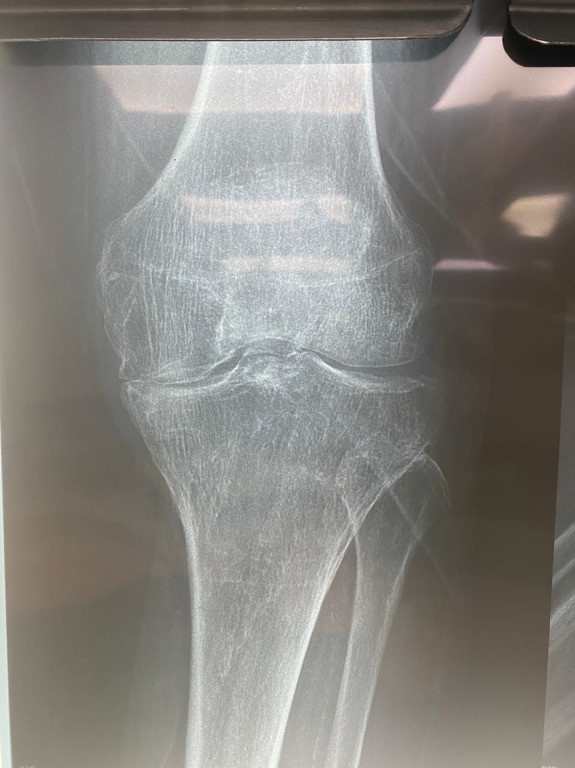

Prótesis total de rodilla

Envíado por Dr. José Israel Flores Hernández